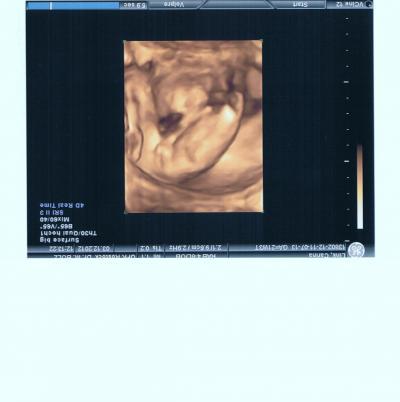

...und was soll ich sagen. Alles ok. Ab sofort mach ich meine Vorsorge nur noch mit meiner Hebi. Zum einen kommt sie zu mir nach Hause. Hab also keine langen Wartezeiten wie bei meiner Ärztin. Herztöne und CTG können wir auf der Couch schreiben. Viel entspannter als auf der harten Pritsche bei Frau Doktor. Nebenbei Kaffee trinken und quatschen. Pipi machen kann ich auch zu Hause. Also was soll ich noch bei meiner Ärztin. Und da ich ja durch meine Zuckerüberwachung eh und je alle 4 Wochen zur ISB muss (werde da ja regelmäßig geschallt), reicht es wenn wir den Rest dann zu Hause machen. War ja gestern wieder bei der ISB zur Feindiagnostik. War alles ok mit meiner Püppi. Geschätztes Gewicht: 330g +/- 50g bei einer Länge von ca. 25-26 cm. Alles im normalen Bereich. Sie hopste reichlich durch ihr zu Hause. Auf jeden Fall hat sich der Verdacht einer Trisomie nicht bestätigt. Püppi ist gesund und munter. Ein kleines Bildchen gab es auch. Mädchen ist nicht zu übersehen. LG Carina

Bild zu Hebammentermin zu Hause... - Forum für April - Mamis